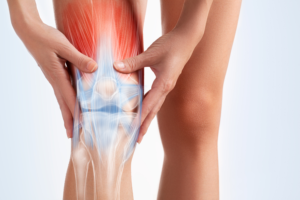

Understand Knee Replacement Surgery: A Guide for Patients in Ahmedabad BestDoctorsInTheCity.com March 11, 2026 Sponsored Knee replacement surgery is a